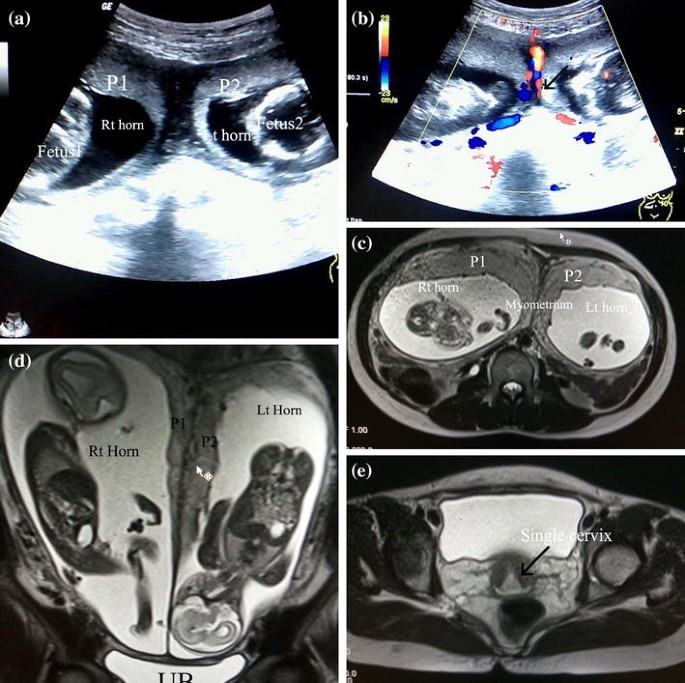

Gale Academic Onefile Document Mri Of A Twin Pregnancy In A Uterus Bicornis Unicollis

Twin Pregnancy In Bicornuate Uterus One Fetus In Each Horn Springerlink

Spontaneous Twin Pregnancy In Uterus Bicornis Unicollis